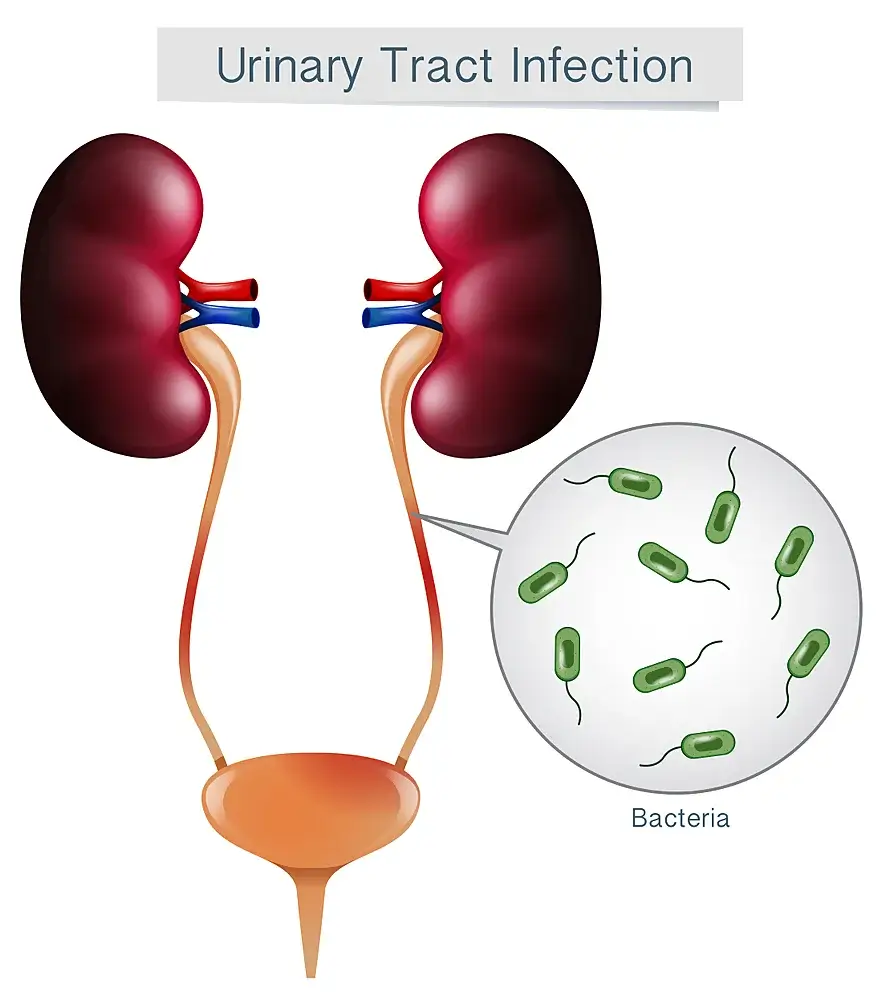

- Urinary Tract Infections (UTI) • Georgetown • Naturopath • Natural Health Clinic of Halton (March 19, 2017)

- Pyelonephritis • Georgetown • Naturopath • Natural Health Clinic of Halton (March 19, 2017)

- Kidneys, Genitourinary/Renal System Conditions • Georgetown • Naturopath • Natural Health Clinic of Halton (March 19, 2017)